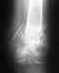

Мой отец Полетаев В.В. 1957 г.р. Пермская обл. г.Соликамск28.12.2004 г. Получил производственную травму при падении с высоты 6 метров. Д-з при поступлении в травм. отделение: перелом костей таза, разрыв симфиза, кресц-позвоночного сочленения слева со смещением.

28.03.2005 г. Компьютерная томография: консолидированный перелом лонной и седалищной костей слева, расширение R-суставной щели лонного сочленения, неконсолидированный вертикальный перелом крестца слева. Спондилолистез L 4-5, циркулярнаяпротрузия дисков L 3-L 4-5, медиальная грыжа диска L5-S, с левосторонней материализацией и компрессией содержимого дурального мешка. Сканированные снимки прилагаются. Боли сохраняются до сих пор, движения ограничены. Возможно ли лечение в вашем институте? Заранее благодарен. Юрий.